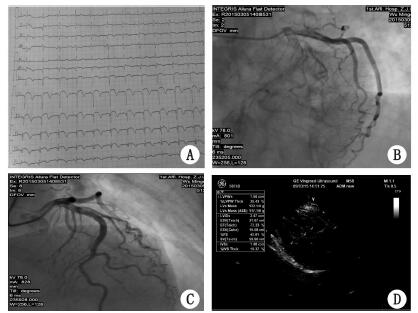

1 资料与方法病例1,女性,72岁,既往有20余年抑郁症史,药物控制。患者1个月前出现胸闷、失眠、纳差伴情绪极度消极,诊断为“重度抑郁症”。经治疗后,突发意识不清,血压下降,心电图示S-T段弓背抬高,肌钙蛋白定量高于正常值,转至我院急诊科。入院时,患者神志清,精神软,主诉胸闷、胸痛,血压110/75 mmHg(1 mmHg=0.133 kPa),心率100次/min,体温37.2 ℃,呼吸20次/min,心电图示Ⅱ、Ⅲ、AVF,V1-V6,S-T段弓背抬高(图 1A)。心肌酶谱示:谷草转氨酶17 U/L,乳酸脱氢酶233 U/L,磷酸肌酸激酶66 U/L肌酸激酶同工酶17 U/L,羟丁酸脱氢酶195 U/L,肌钙蛋白定性阴性。考虑急性广泛前壁心肌梗死,急诊行冠状动脉造影示:左主干未见明显狭窄,左前降支远段30%狭窄,左回旋支未见明显狭窄,右冠脉近中段35%狭窄,中段20%狭窄(图 1B)。心脏B超示:左室心尖部室壁增厚正常范围,室壁呈反向运动,室间隔基底部增厚1.3 cm,左室舒张功能减退提示:符合心尖气球样表现(图 1C)。实验室检查:肌钙蛋白I定量0.352 ng/mL,心肌酶谱谷草转氨酶19 U/L,乳酸脱氢酶197 U/L,磷酸肌酸激酶61 U/L肌酸激酶同工酶15 U/L,羟丁酸脱氢酶183 U/L。住院期间服用阿司匹林、氯吡格雷抗血小板,硝酸甘油抗血小板、抗心肌缺血等治疗后,症状好转出院。

| 图 1 病例1 心电图(A)、冠脉造影(B、C)和心脏超声结果(D) |